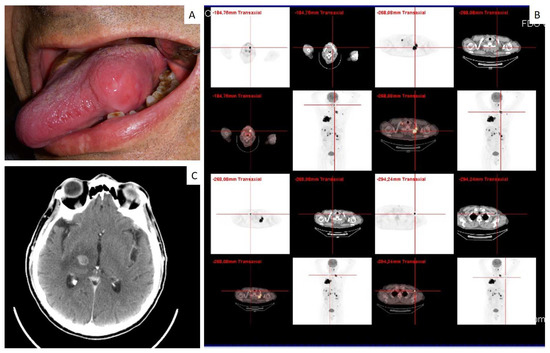

| 19 | 65 | F | Tongue | Small cell carcinoma | n.a. | Yes |

| 21 | 66 | M | Tongue | Small cell carcinoma | Brain | No |

| 2 | Non small cell carcinoma—unclassifiable (undifferentiated carcinoma) | −/+ | +/− | − | − | − | − | +/− | − | − | − | − | − | − | − |

| 21 | Small cell carcinoma | − | + | − | − | − | − | + | − | + | + | − | − | − | − |